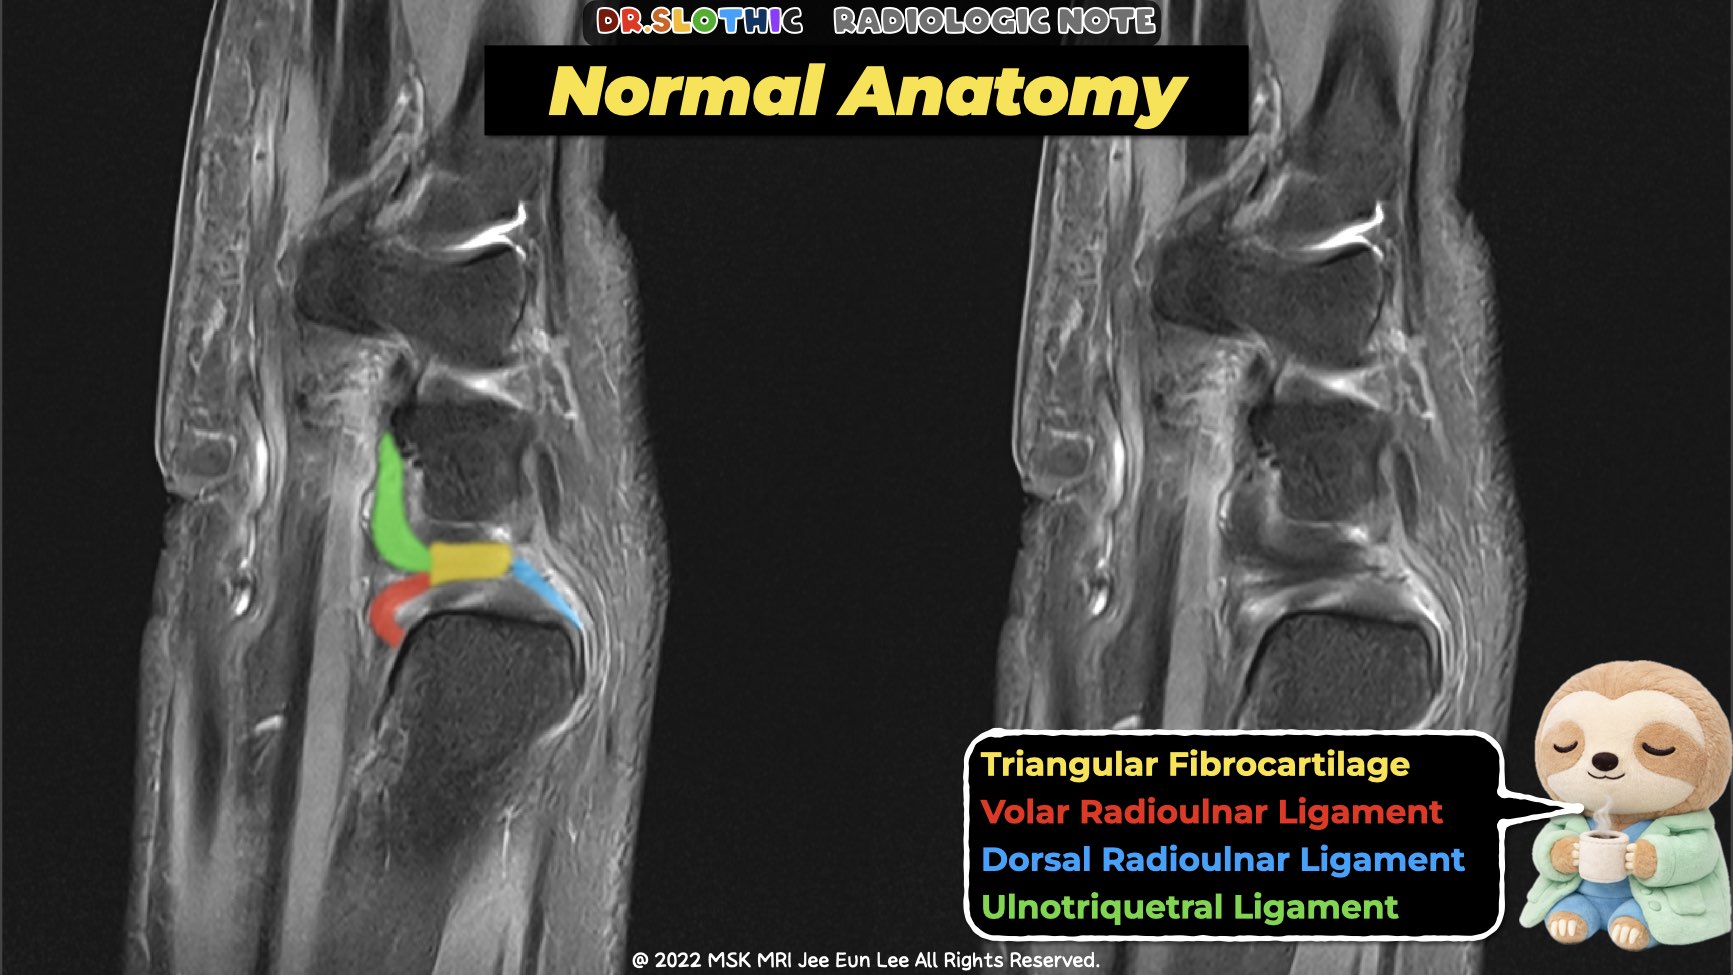

On sagittal wrist magnetic resonance imaging,

the triangular fibrocartilage complex should not be read as a single disc.

It represents a continuous ulnar-sided stabilizing system connecting the distal radioulnar joint to the ulnocarpal joint.

Ulnocarpal Ligaments (Distal Continuation)

Ulnolunate Ligament

- Palmar ligament extending from the volar radioulnar ligament region

and indirectly from the ulnar fovea or styloid base. - Inserts on the palmar cortex of the lunate.

- Courses distally along the long axis of the forearm.

- Helps suspend the lunate and resist palmar and ulnar translation of the proximal carpal row.

Ulnotriquetral Ligament

- Palmar ligament arising mainly from the volar radioulnar ligament,

with partial contribution from the palmar-ulnar aspect of the ulnar styloid. - Fans out distally to the proximal and ulnar surfaces of the triquetrum.

- Lies just ulnar to the ulnolunate ligament.

- Contributes to ulnocarpal stability and load transmission from the ulnar carpus to the ulna.

MRI Take-Home Message

On sagittal wrist magnetic resonance imaging:

disc → radioulnar ligaments → ulnocarpal ligaments

should be followed as one continuous stabilizing chain.

Instability rarely comes from the disc alone.